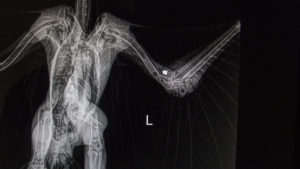

GSW HaHa

August 26, 2018/by Terry Stevens